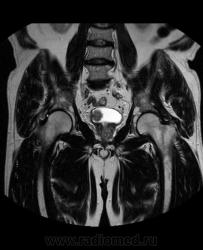

Для динамического контрастирования требуется инъектор, у нас с ним технические неполадки, поэтому контрастное вещество вводим от руки. Но в данном случае четко видно проростание опухолевого компонента через мышечный слой мочевого пузыря, даже некоторой инфильтрацией паравезикальной клетчатки. По гистологии плоско-клеточный рак. У пациента множественные метастазы в легких.